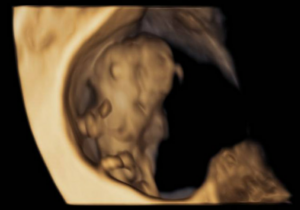

The ultrasound images demonstrated a single spinal column, two stomachs, and two hearts (Figure 2A). Two fused abdomens were observed, along with subcutaneous edema measuring 2.0 mm and 2.1 mm (Figure 2B). In addition, two pairs of moving legs were identified (Figure 2C). The trophoblast was located anteriorly, and a single corpus luteum was observed in the left ovary. Two follow-up examinations were required at 9 and 10 weeks of gestation to establish the diagnosis. At 9 weeks of gestation, the 3D ultrasound images lacked sufficient clarity for a definitive diagnosis (Figure 3). At 10 weeks of gestation, color Doppler imaging demonstrated two distinct cardiac activities, indicating the presence of two separate circulatory systems (Figure 4A). Three-dimensional imaging further revealed the face of one of the conjoined twins and confirmed the presence of two umbilical cords (Figure 4B).